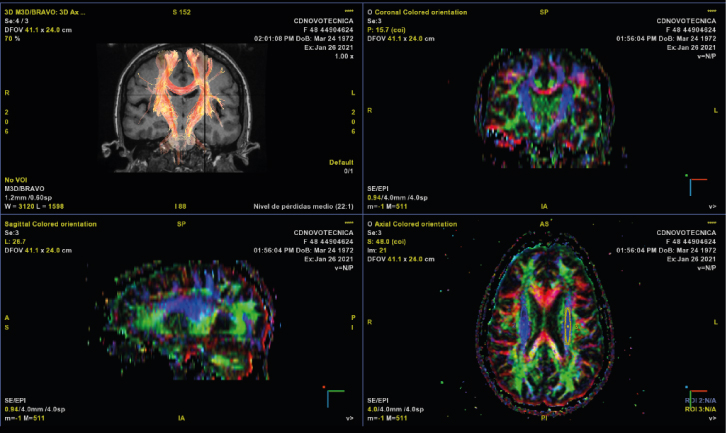

TENSOR DE DIFUSIÓN

Mediante unos mapas de colores la difusión permite realizar una tractografía permitiendo valorar especialmente los tractos de sustancia blanca a nivel cerebral y realizar un mapa de la red de fibras nerviosas. Entre sus aplicaciones fundamentalmente permite valorar isquemia cerebral, enfermedades desmielinizantes, epilepsia, patología tumoral y se está empezando a estudiar en demencias y trastornos neurodegenerativos.